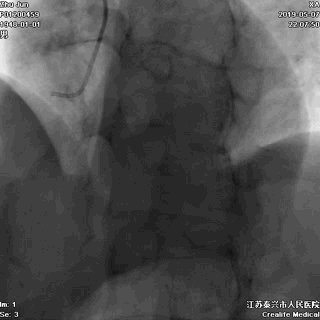

右冠状动脉无严重病变